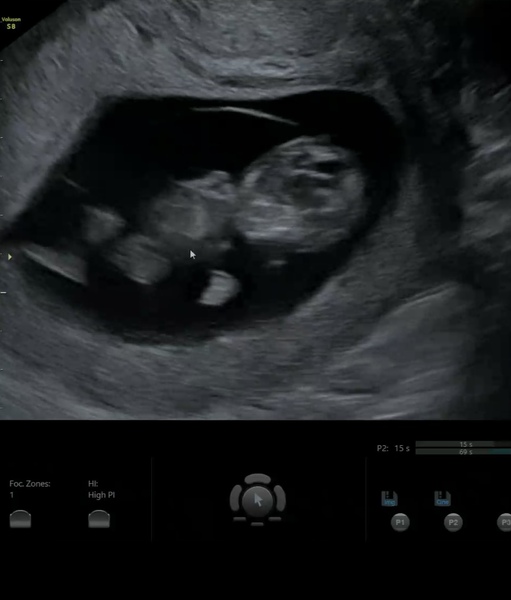

How did your scan go on the weekend? I had one on Saturday. Was amazing. They dated me a little ahead (10+3 on Saturday), so supposedly 10+5 today. But 10+1 by my own dates so will see.

Have attached a pic of Saturdays scan 🥰